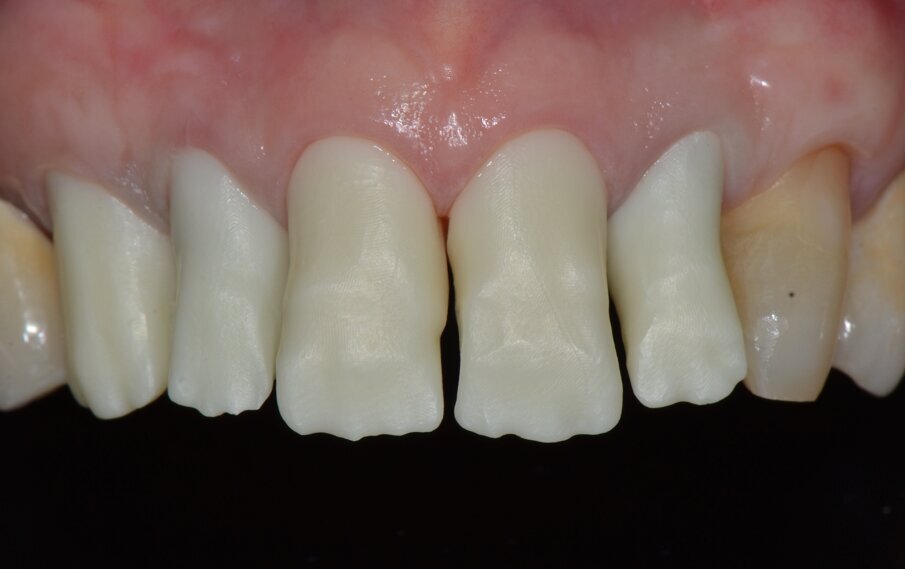

Da un punto di vista protesico verranno eseguite corone singole in zirconia stratificata sugli elementi 13-12-11-21-22 e una faccetta in disilicato di litio sul 23. A causa della notevole rotazione dei due incisivi centrali in fase di ceratura abbiamo optato per due corone complete anziché due faccette per una migliore distribuzione degli spazi protesici dei quattro incisivi (Fig. 8). Il gruppo frontale inferiore invece verrà protesizzato con corone in zirconia stratificata sugli elementi 32-31-41-42-43 splintate per compensare una mobilità di grado 1 dei quattro incisivi.

Inizialmente vengono applicati i provvisori prelimatura (Fig. 9) utilizzati anche come mock-up per passare dopo le opportune valutazioni estetiche (Figg. 10, 11) a una seconda serie di provvisori che ci accompagnaranno durante la fase chirurgica e il tempo di guarigione e maturazione dei tessuti. Prima si procede con la chirurgia resettiva (ORS) sul canino superiore destro per alzare la parabola gengivale a livello degli altri denti frontali; questo intervento viene eseguito con un approccio “delicato” e meno invasivo possibile per non penalizzare l’estetica della corona preesistente sul primo premolare superiore destro.